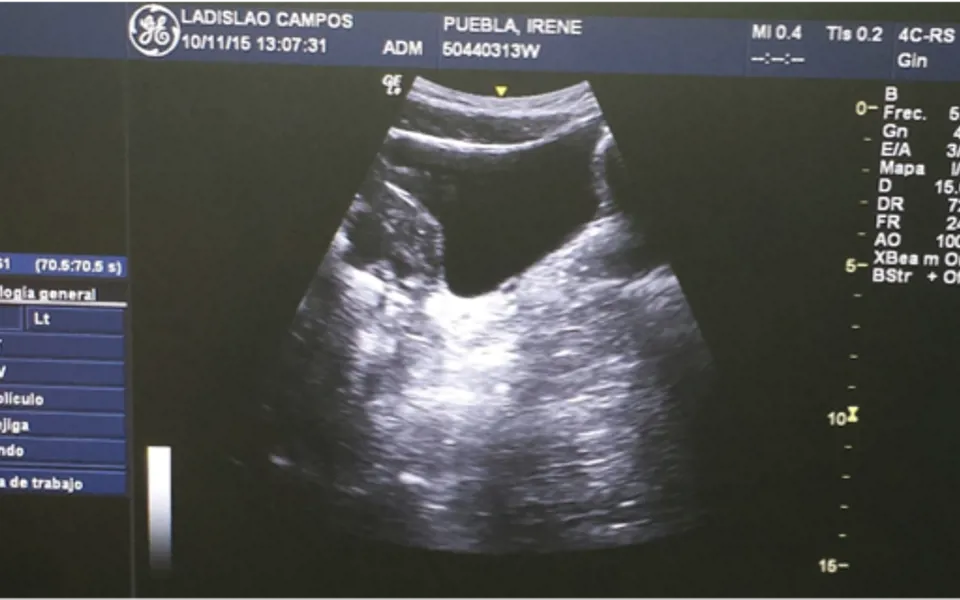

La ecografía permite la observación de la contracción de la musculatura del suelo pélvico, tanto al fisioterapeuta como al paciente. La siguiente imagen muestra un corte sagital de una ecografía transabdominal realizada en nuestra clínica.

En esta imagen, se observa la vejiga de perfil y la contracción nos permite observar el movimiento ascendente del suelo pélvico cerrando la uretra.